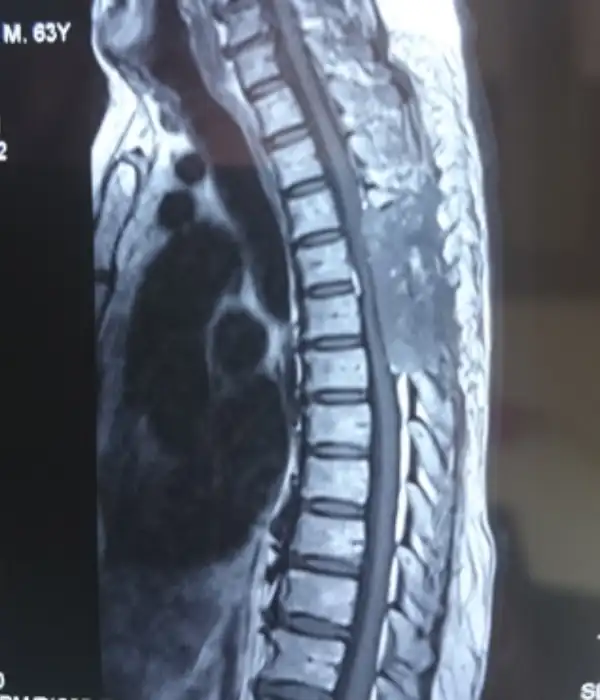

Degenerative Thoracolumbar Spine Disorders

Degenerative thoracolumbar disorders are becoming increasingly prevalent as patients have longer, healthier, and more active lives. While much of the treatment is nonsurgical, there are certain conditions that require surgery. Some degenerative diseases can be easily treated with small, minimally invasive procedures, but others require large, reconstructive operations. The spine surgeons at Kauvery Advanced Spine Centre have considerable experience treating the entire spectrum of degenerative disorders, as well as in-depth knowledge of the success rates of each procedure. Mini open and minimally invasive transthoracic disc surgery is performed here.